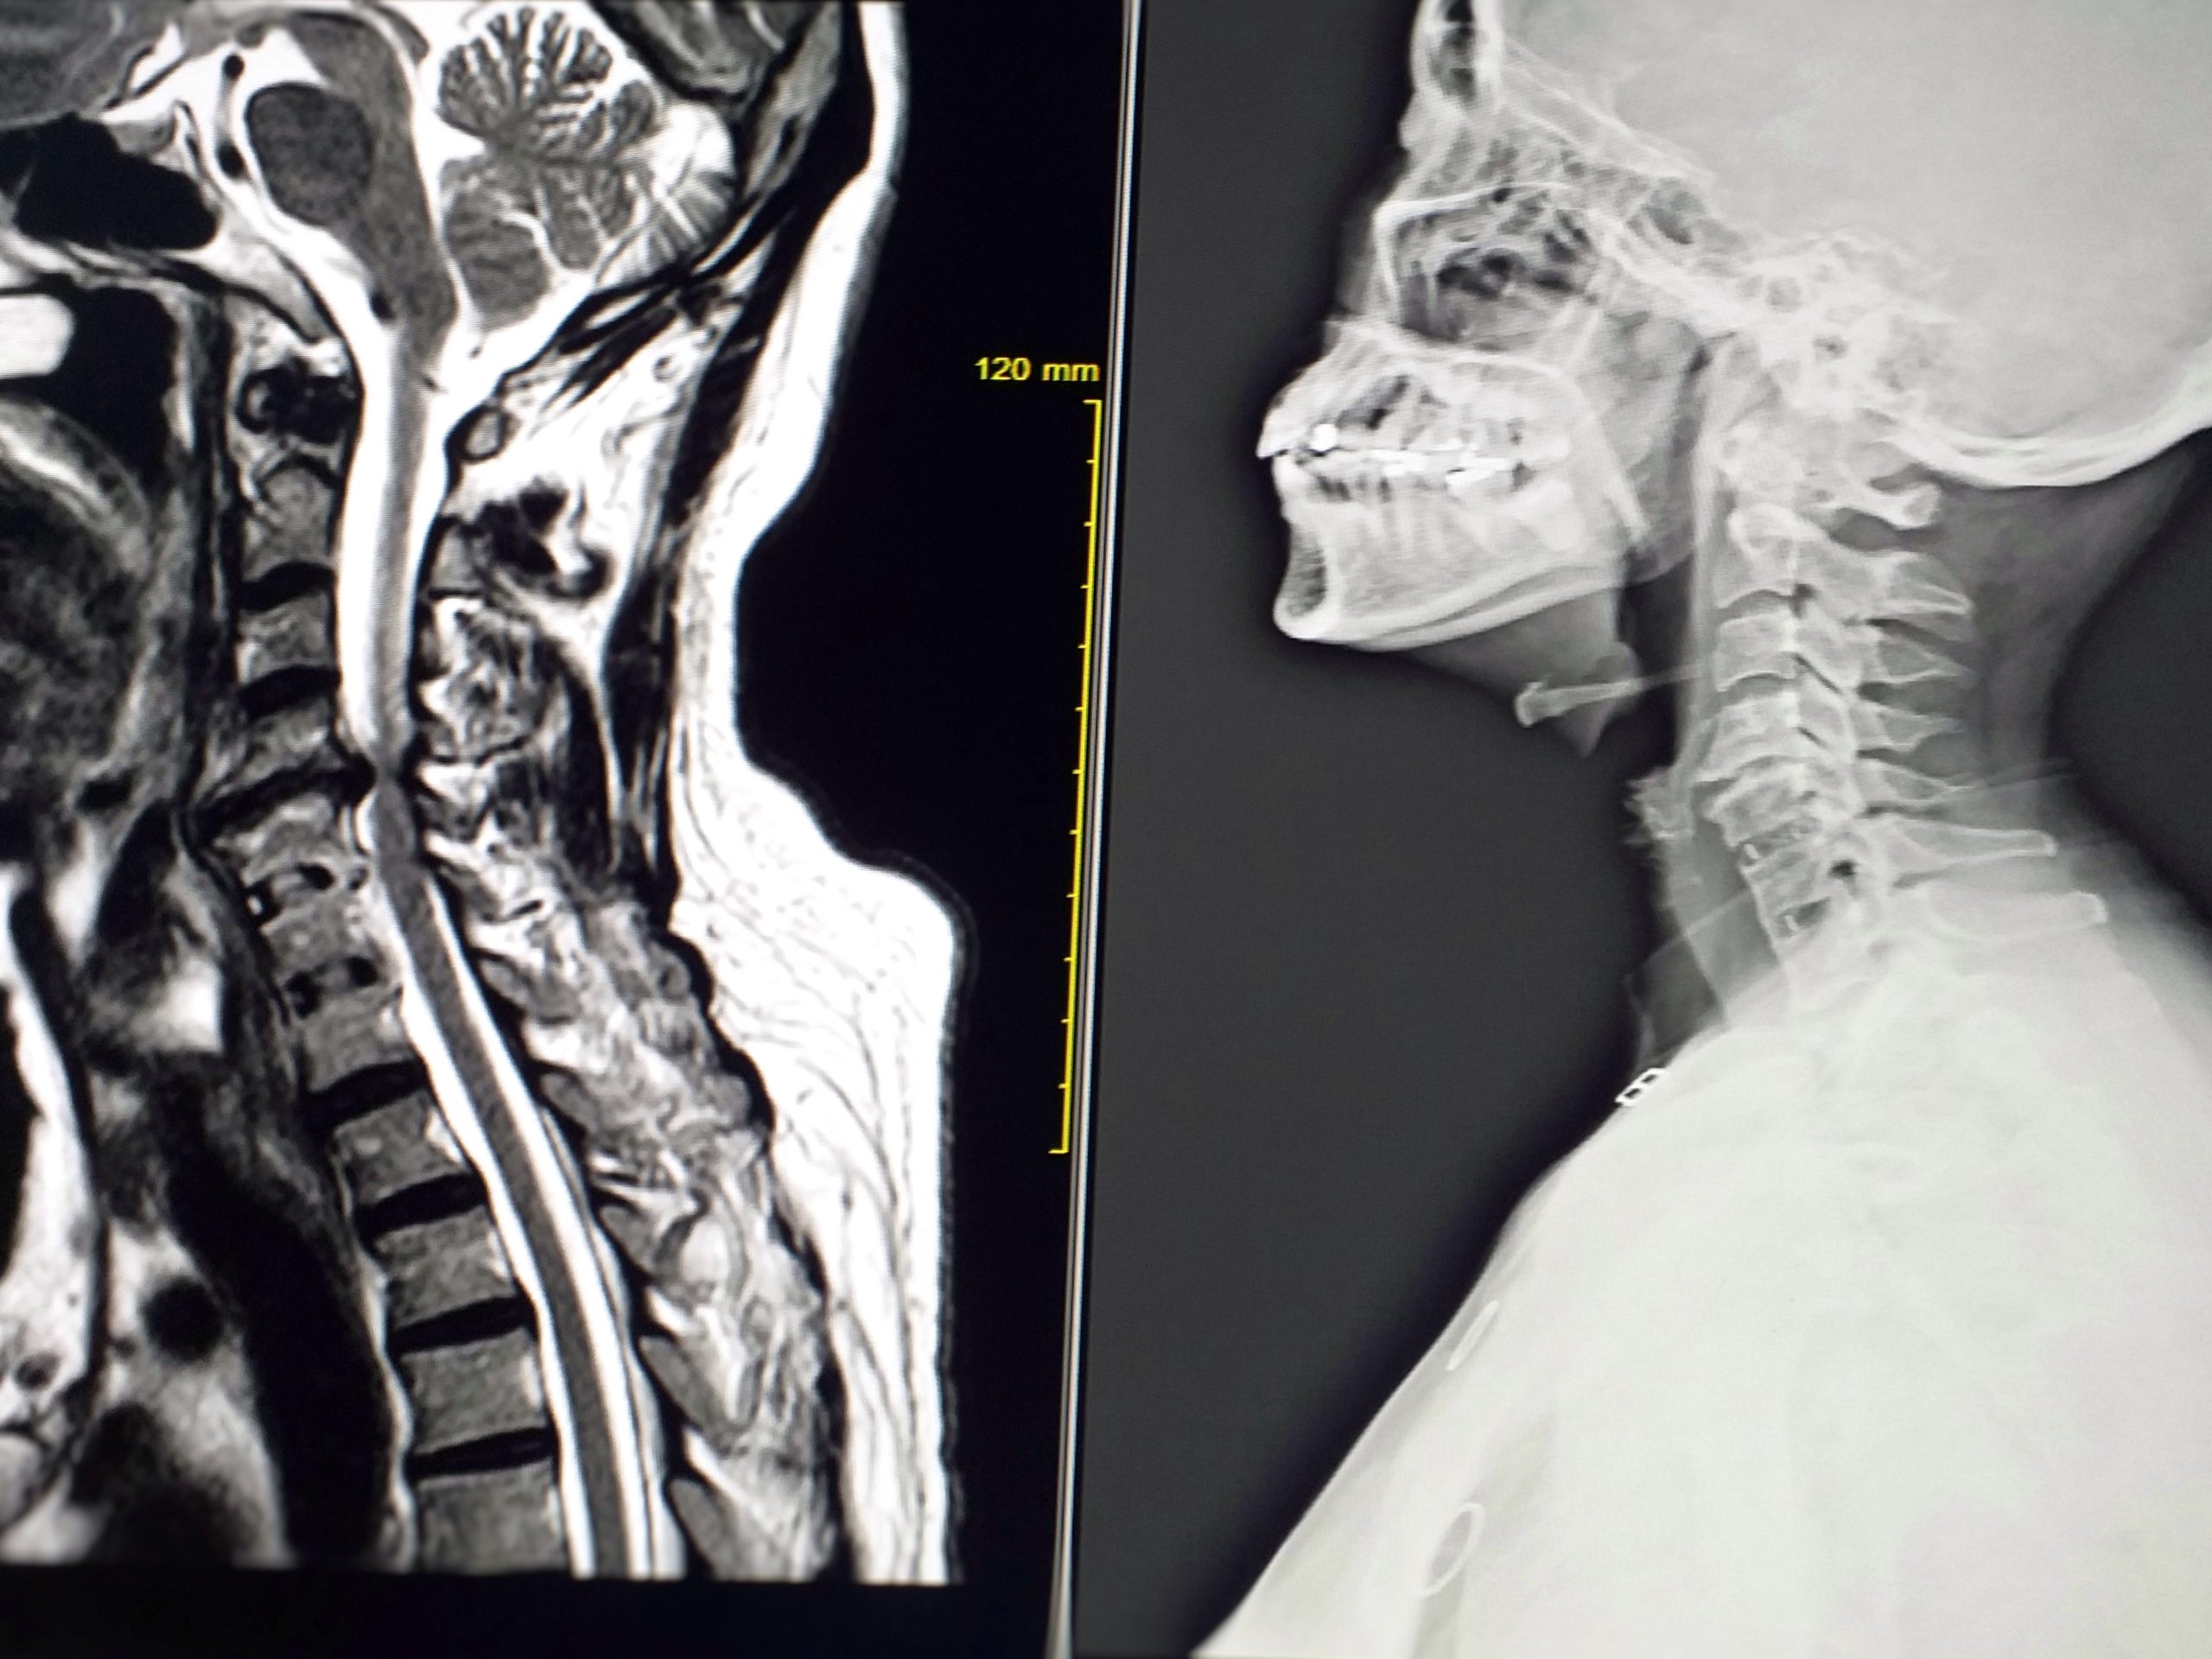

Spine-related extremity pain, particularly involving the cervical region, presents a complex clinical challenge due to its heterogeneous nature and overlapping symptomatology. Accurate diagnosis and t...

Management of cervical radicular syndromes can involve surgical or conservative approaches. Evidence suggests that while surgery may provide faster pain relief compared to physical therapy or hard-col...